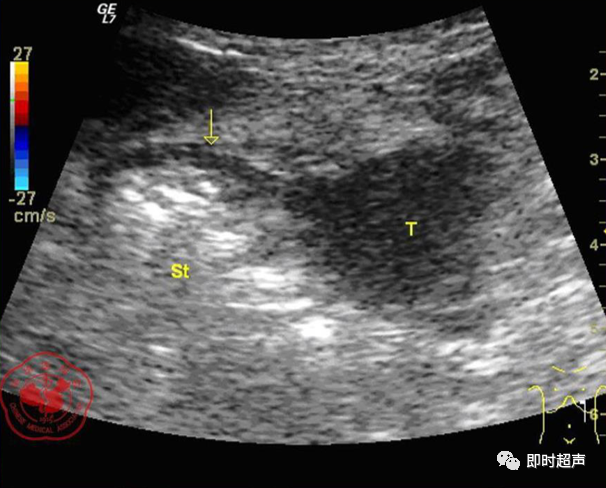

• GIST的发病机制与KIT信号通路的激活有关。• KIT是一种酪胺酸激酶跨膜受体蛋白,未经“装配”过的KIT蛋白是一种非活化的单体,参与细胞膜形成。几乎所有GIST都表达了KIT蛋白,而且大多突变的KIT基因保留了表达KIT蛋白的特性。c-kit内的突变主要见于恶性病例,特别是外显子11的点突变,还有外显子9、13和17,可以导致本质的或配体独立的c-kit激活,引发细胞的无序增殖和凋亡。这些具有功能的突变是GIST发病机理的关键,并且与肿瘤的恶性程度和预后较差相关。• GIST约75%发生于50岁以上老年人,中位年龄为58岁,无明显差异。• 可以发生在消化道从食道到肛门的任何部位,偶尔可原发于网膜、肠系膜和腹膜后,约50%发生在胃,25%发生在小肠,不足10%发生于食管、结肠及直肠。大体观察:肿块多境界清楚,类圆形,结节状,部分有假包膜。切面灰白、灰红,质韧,部分质嫩呈鱼肉状,伴有出血、坏死、囊性变。• 肿瘤组织主要由两种细胞组成,一种为长梭形细胞,细胞质丰富,嗜酸性,细胞核呈梭形或杆状;另一种为上皮样圆形或多角形细胞,细胞肥胖,胞质少。两种瘤细胞常呈束状、编织状或旋涡状排列。• 部分病例细胞异型明显,核分裂象增多,可见病理性核分裂象和瘤巨细胞。梭形细胞界不清楚,胞质丰富,淡染,轻度嗜伊红或略嗜碱,可有纤细、长梭形、短梭形或胖梭形、卵圆形,可见核仁。细胞核两端钝圆,部分病例胞质呈空泡状,位于核一端形成核端空泡胞,多呈交叉束状、旋涡状、席纹状及栅栏状排列。上皮样细胞胞浆丰富或透亮,多呈弥漫片状、束状或巢状排列。肿瘤间质可有出血、囊性变、坏死及黏液变,可见炎性细胞浸润。CD34抗原是一种115kd的糖基化蛋白,50%~80% GIST的CD34表达为阳性,CD34对鉴别GIST和典型的平滑肌瘤,神经鞘瘤还是非常有用的标记物,因后两者的CD34一般是阴性的。但CD34在诊断GIST上其特异性受到限制,一般情况下CD34多与CD117联合应用,方能提高GIST的诊断率。• 与肿瘤大小、发生部位、肿物与肠壁的关系以及肿瘤的良恶性有关。• 肿瘤较小者(直径小于2cm)常无症状,往往在体检和其它手术时无意中发现。• 肿瘤发生于胃肠道腔内时大多表现为呕吐、腹痛及消化道出血,而发生于胃肠道腔外的则主要表现为腹部包块。• 最常见的临床症状是中上腹部不适、腹部肿块及便血。• 对于临床发现的消化道(包括肠系膜、网膜、后腹膜)实体肿瘤,在排除其他常见肿瘤后,才考虑GIST。目前,诊断GIST有三条标准:③肿瘤组织具有梭形细胞和上皮样细胞两种基本细胞成分的病理学特征。这是诊断GIST金标准。CD117阳性者或CD117阴性而CD34阳性者,且伴平滑肌和神经双向分化或无分化者,可诊断为GISTs;以Desmin和SMA强阳性,而CD117阴性诊断为平滑肌肿瘤;以S-100阳性,CD117、Desmin、SMA均阴性诊断为神经鞘瘤。• GISTs的分型与组织学良恶性的关系:研究证实GISTs非单一分化的肿瘤,具有多向分化。• 当前GISTs的良性、交界性和恶性判断标准多参照Amin等提出的标准:②交界性:核分裂<5/50HPF,但肿瘤>5cm;• 另外研究显示,平滑肌型大多数为良性,少数为交界性和恶性,神经源型为恶性,双向分化亚型和未分化型为交界性和恶性,提示GISTs的分化型与其良恶性之间有一定关系。• 胃间质瘤早期多局部侵犯,后期出现肝转移和腹腔内种植,小肠间质瘤早期即可出现转移• 主要有超声扫描(检出率30%左右)、纤维内镜、超声内镜、CT、MRI、普通X• 线检查(胃肠钡餐造影、小肠插管气钡双重造影)、选择性血管造影检查等。• 不同部位的GIST,各种检查方法的敏感性不同。以CT检查为佳,尤其是螺旋CT,分辨率最高,可以三维重建,直接显示肿瘤大小、形态、密度、内部结构、边界,对邻近组织的侵犯也看得很清楚,同时还可观察其他部位的转移灶,有利于分期、鉴别与诊断。• MRI具有多轴成像及反映肿瘤内部成分的优点,尤其是动态扫描及各种新的扫描系列的出现更使其可以普及应用。• DSA检查对于GIST,特别是有消化道出血的患者更有价值。• 上述影像学检查表现并非特异性,与胃肠道平滑肌肿瘤、神经源性肿瘤鉴别困难。明确诊断要依赖病理免疫组化等手段。• 超声图像特征 肿物体积较小者(直径< 5. 0 cm )多为实性病变, 呈类圆形, 边界清晰, 内部回声多为较均匀的低回声。• 肿物体积较大者(直径> 5. 0 cm ) 多为混合性病变,呈不规则圆形或分叶状, 多数边界尚清晰, 以实性为主的病变内部为不均质中低回声伴不规则液性区及斑点状强回声; 以囊性为主的病变囊壁较厚,有分隔, 部分囊腔内可见点状、团状低回声。CDFI显示肿物实质回声内血流均较丰富。病例1:患者男, 62岁。自扪腹部包块2月余,包块增大20天就诊。查体:腹部平坦,无腹壁静脉曲张,无胃肠型及蠕动波,腹肌软,剑突下5cm处及左肋缘下可触及一质韧包块,大小约15*12cm,活动度差,边界尚清,包块深压痛,全腹无反跳痛。化验检查AFP:3.66(1.09-8.04)ng/ml,CEA:2.85(0-5)ng/ml。体格检查:一般情况良好,全腹软、平坦,腹部无压痛。超声检查:患者仰卧位时左上腹于胰尾前方可见一大小约6. 1 cm ×5. 8 cm ×5. 3 cm实性均质低回声,形态规则,包膜完整,边界清晰,活动度大;右侧卧时,肿块移至胰头右前方(图1) ;于其内探及丰富血流信号。体格检查:一般情况良好,腹丰满,上腹部有轻压痛,未扪及明显肿块。超声检查:患者仰卧位时左上腹于胰尾前方、脾门处可见一大小约10. 0 cm×8. 8 cm×7. 6 cm 实性低回声(图2) ,形态规则,包膜完整,边界清晰,肿块活动度大;右侧卧时,肿块移至左肝下间隙,回声尚均质;于其内探及较丰富血流信号(图3) 。图3 腹腔低回声肿块位于左肝下间隙,于低回声肿块内探及较丰富血流信号向壁外生长的胃肠道间质瘤, st为胃腔,箭头所指为胃壁, T为向外生的肿瘤• 胃间质瘤的定位准确率要高于十二指肠及小肠间质瘤,这主要是因为胃的解剖位置相对固定,且通过饮水使胃腔充盈,可清晰的显示胃壁的各层结构及肿块与胃壁的关系。肿块多表现为粘膜下、肌层或浆膜下低至中等回声团块,可向腔内、腔外或腔内外生长。但当肿瘤较大或浸润周围脏器时,超声定位仍有困难, 因此,超声如发现上腹部肿块且怀疑来源于胃者,应尽可能嘱其饮水充盈胃腔,并多角度、多切面观察肿块与周围脏器的关系,以提高定位的准确性。• 十二指肠间质瘤的定位亦较准确,但降部的外生性肿块常与胰头粘连而误诊为胰腺肿瘤回声均匀且位置较深的间质瘤亦可能误为胰头周围淋巴结。• 空、回肠间质瘤常因肿块较大,多发,位置不固定而难以定位,往往误诊为腹、盆腔或腹膜后肿瘤,超声检查如发现肿块局部肠壁增厚,肿块与肠道随呼吸同步运动时可作出定位诊断。• GIST的声像图表现有助于其良、恶性的鉴别:良性肿瘤多体积较小,圆形或椭圆形,回声均匀,边界清晰。恶性肿瘤多较大,呈不规则分叶状,回声不均匀,内部易出血、坏死、囊变。• 肿瘤长径与肿瘤内部是否出现无回声区在良、恶性病变之间的差异有统计学意义,是判断良恶性的有效征象。• 如以肿瘤长径>5cm为诊断恶性标准,其敏感性、特异性及准确性均较理想。超声可为临床提供胃肠道间质瘤的部位、大小、边界、回声等较多有用信息,一部分病例可作出定位、定性诊断,并可在术后或复发患者药物治疗期间对其进行动态观察;CDFI方便快捷、无需造影剂即可对间质瘤周边及内部血流进行观察,可为临床医师提供肿瘤血供情况。但未发现腹腔或肝脏转移时,超声判断胃肠道间质瘤性质有一定难度。• 目前临床上对GISTs的治疗效果并不十分满意。治疗仍以手术为主,对无法手术切除或已有转移的GISTs患者进行甲磺酸伊马替尼化疗。• 手术方式取决于肿瘤大小、部位和术中冰冻切片结果等。• 发生在胃的间质瘤,可首选胃大部切除术;发生在十二指肠的间质瘤可行保留胰头的十二指肠切除术或胰十二指肠切除术;发生在小肠的间质瘤可行肿瘤肠段切除术;发生于结肠的间质瘤可行左半或右半结肠切除术;发生于直肠的间质瘤可行肿瘤局部切除术。一般情况下无需淋巴结清扫。• 术后随访监测,复发者单个病灶可考虑手术切除;多发或转移特征者应试行甲磺酸伊马替尼化疗,并监测肿瘤大小及数目的改变。• 随着分子靶点药物进入肿瘤临床,一种小分子化合物———酪胺酸激酶受体抑制剂,美国称为Gleevec,欧洲叫做Glivec(格列卫),在治疗GIST和慢性粒细胞白血病方面有其独特的作用。已知细胞膜表面上皮生长因子受体酪胺酸激酶抑制剂大致分为两大类:一类是小分子化合物;另一类是特异性抗体。利用抑制酪胺酸激酶的活性,对处于增殖期状态的病变具有治疗的作用。Glivec在体外、体内和细胞水平都可强烈抑制酪胺酸激酶的活性,是干细胞因子(SDCF)受体KIT的强抑制剂。• Glivec推荐用量为400mg(4片),每日一次, 3个月为一疗程。如服3个月后无效可加至600mg/d~800mg/d(6~8片)[18];若仍无效果不再增量应停止治疗。• Glivec治疗进展转移的GIST总有效率为50%左右,比传统化疗有效率高十倍以上;肿瘤生长控制率达80%以上,起效最快在服药后24h之内,使症状改善如疼痛缓解;平均起效时间为13周(约3个月)。患者体力状况改善是又一突出效果。2/3患者治疗后无症状可如健康人生活工作。• Brainard等研究发现间质瘤预后差的前两位因素为肿瘤大小和核分裂象,故对于间质瘤直径>5cm和核分裂象>5/50HPF的患者应给予口服Glivec。最近,Liu报道口服Glivec治疗可使85%患者的病情得到控制。